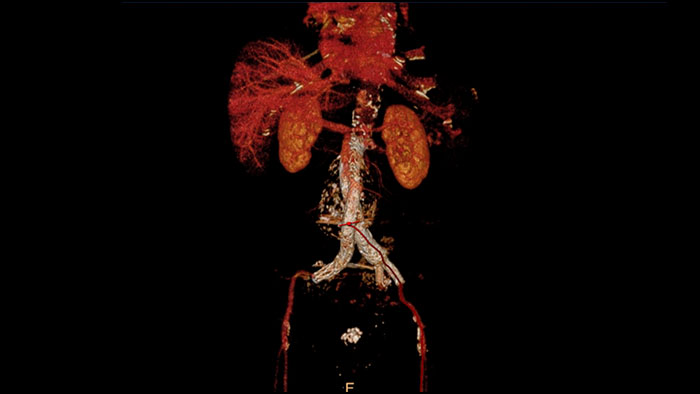

Comprehensive vascular analysis planning

Designed to examine and quantify different types of vascular lesions from CTA and MRA scans. It accommodates different modes of inspection, allows labeling different vascular lesions, and helps navigating through multiple findings. Demonstrated to reduce the post-processing time by 50% when compared to manual Head & Neck CT angiography (CTA) analysis*.

Benefits

* Ardley N et al. Efficacy of a new post processing workflow for CTA head and neck. ECR 2013 / C-1760.